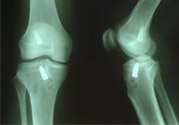

1、部分?jǐn)嗔眩宏P(guān)節(jié)內(nèi)無積血,外翻位X線片顯示內(nèi)側(cè)關(guān)節(jié)間隙不大,可做局部封閉、彈性繃帶加壓包扎,早期鍛煉股四頭肌或用踝上長腿石膏托固定于膝內(nèi)翻和稍屈位3—4周,石膏完全干后可開始股四頭肌鍛煉和下地行走。

2、完全斷裂:原則上應(yīng)行手術(shù)治療如韌帶斷裂,可直接縫合;如骨附著處撕脫,可用鋼絲貫穿法固定或直接縫合于骨膜及軟組織上。如有撕脫骨片,則用鋼絲或螺絲釘固定。如合并半月軟骨損傷,應(yīng)予以切除。合并前膝交叉韌帶損傷者,應(yīng)先修補(bǔ)。術(shù)后石膏固定4—6周。

4、膝交叉韌帶損傷:前交叉韌帶合并脛骨棘撕脫骨折者,可用膝過伸和后推脛骨使之復(fù)位,用長腿石膏固定4—6周。對(duì)于未能復(fù)位者,應(yīng)及時(shí)手術(shù)修補(bǔ)。將骨折片用鋼絲固定。單純韌帶斷裂者,用石膏固定。對(duì)陳舊性損傷,以保守治療為主,經(jīng)鍛煉后,關(guān)節(jié)仍不穩(wěn)定,亦可考慮手術(shù)修補(bǔ)。后交叉韌帶可不修補(bǔ)。